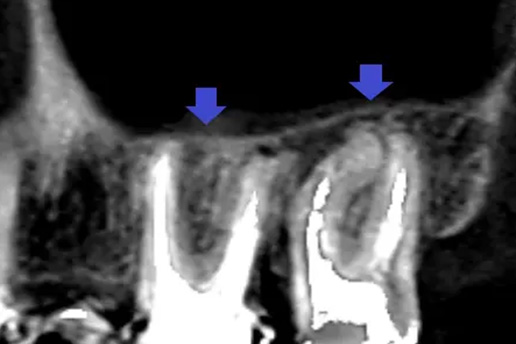

■歯周病の再生療法

歯周病が原因であごの骨が溶けてしまい歯がグラグラしていたケース。

再生療法で骨を再生させ抜歯せずに治療できた。